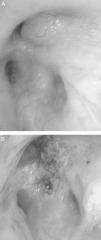

CasosCaso 1Varón de 46 años que consultó por tos no productiva, disnea de moderados esfuerzos de nueva aparición y fiebre de 38°C. Como único antecedente, fumador de 45 paquetes/año sin criterios clínicos de bronquitis crónica. En la exploración física destacaba saturación basal de oxígeno medida por pulsioximetría (SpO2) de 93% respirando aire ambiente, y en la auscultación pulmonar roncus en ambos hemitórax. La radiografía de tórax mostró una condensación alveolar en la base derecha e incipiente en el ápex izquierdo, y una imagen nodular en el segmento apical del lóbulo inferior izquierdo. En la analítica sanguínea presentaba leucocitosis de 17,6×109/l con neutrofilia del 86% y una proteína C reactiva de 19mg/dl. Ante la sospecha de neoplasia pulmonar, se realizó una tomografía computarizada (TC) de tórax que mostró imágenes en vidrio deslustrado en el lóbulo superior izquierdo y en segmentos posterobasales de ambos lóbulos inferiores, así como múltiples imágenes nodulares (centroacinares) y de árbol en brote, localizadas en el segmento apical del lóbulo inferior izquierdo y en segmentos posterobasales con tendencia a conglomerarse, sin formaciones adenopáticas. Se realizó fibrobroncoscopia, que evidenció una obstrucción >80% de la luz de los bronquios B1-B6D por infiltración de la submucosa y lesiones nodulares (fig. 1A), así como una estenosis irregular de los bronquios basales derechos. Además presentaba un ensanchamiento carineal y estenosis traqueal en el tercio superior. La biopsia mostró epitelio respiratorio con depósitos de material amiloide que, tras la realización de técnicas inmunohistoquímicas con rojo Congo, se confirmó como amiloidosis. Se realizó estudio de extensión, descartándose enfermedad sistémica, por lo que se estableció el diagnóstico de amiloidosis primaria traqueobronquial localizada.

El paciente del caso 1 fue tratado en 2 ocasiones con láser Nd:YAG para la repermeabilización de la vía aérea (fig. 1B), debido a la estenosis que presentaba por infiltración amiloide, con lo que se consiguió una mejoría clínica y funcional del paciente. En cuanto a la paciente del caso 2, recibió tratamiento con una combinación de prednisona y melfalán, con buena respuesta y resolución parcial de las lesiones traqueales sin afectación funcional ni sintomática.